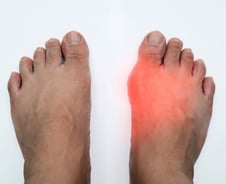

통풍은 혈액 내 요산이 쌓이면서 관절과 주위 연부조직에 요산염이 발생하는 질병이다. 40~50대 남성에서 가장 많이 발생하는데, 출산의 고통(통증지수 10)에 버금갈 정도의 극심한 통증을 동반한다. 대부분 엄지발가락에서 발생하고, 발목·무릎에서도 나타난다. 통풍의 원인인 요산은 음식에 든 퓨린(피린미딘과 이미다졸이 융합된 형태의 화합물)이 분해되면서 생기는 찌꺼기다. 치료를 위해서는 요산의 축적을 억제하거나 소변으로 배출하는 게 가장 중요하다. '요산저하제'를 먹어 요산 수치를 떨어뜨린다(요산저하치료). 통풍은 수술·시술 치료법이 없어 평생 '약'으로만 관리해야 한다. 의정부을지대병원 류마티스내과 손창남·오윤정 교수에게 요산저하제 복용 시 주의사항, 식단 등에 대해 들었다. ━요산저하제 먹는 사람, 약 끊으면 대부분 재발━요산저하제는 언제 먹어야 하는 걸까? 손창남 교수는 "1년에 두 번 이상 통풍으로 발작이 일어날 때 요산저하치료를 시작해야 한다"고 설명했다. 다만, 만성질환이 있